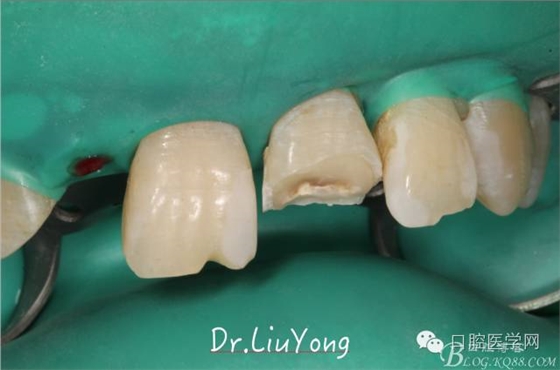

手術(shù)后1月,決定先行臨時(shí)修復(fù),由于患者為重度深覆合,因此考慮將上前牙通過(guò)臨時(shí)修復(fù)體,降低切端的高度,減輕覆合,同時(shí)將舌傾的牙冠形態(tài)調(diào)整為較為直立。B2為根折到齦下1.5mm,考慮到患者無(wú)法接受正畸,同時(shí)如果近中鄰面行冠延長(zhǎng)手術(shù)會(huì)帶來(lái)后續(xù)的黑三角美觀問(wèn)題,因此選擇在橡皮障下行齦壁提升,然后A2纖維樁+樹脂核,A1-B2臨時(shí)樹脂貼面修復(fù),A2臨時(shí)冠修復(fù)。